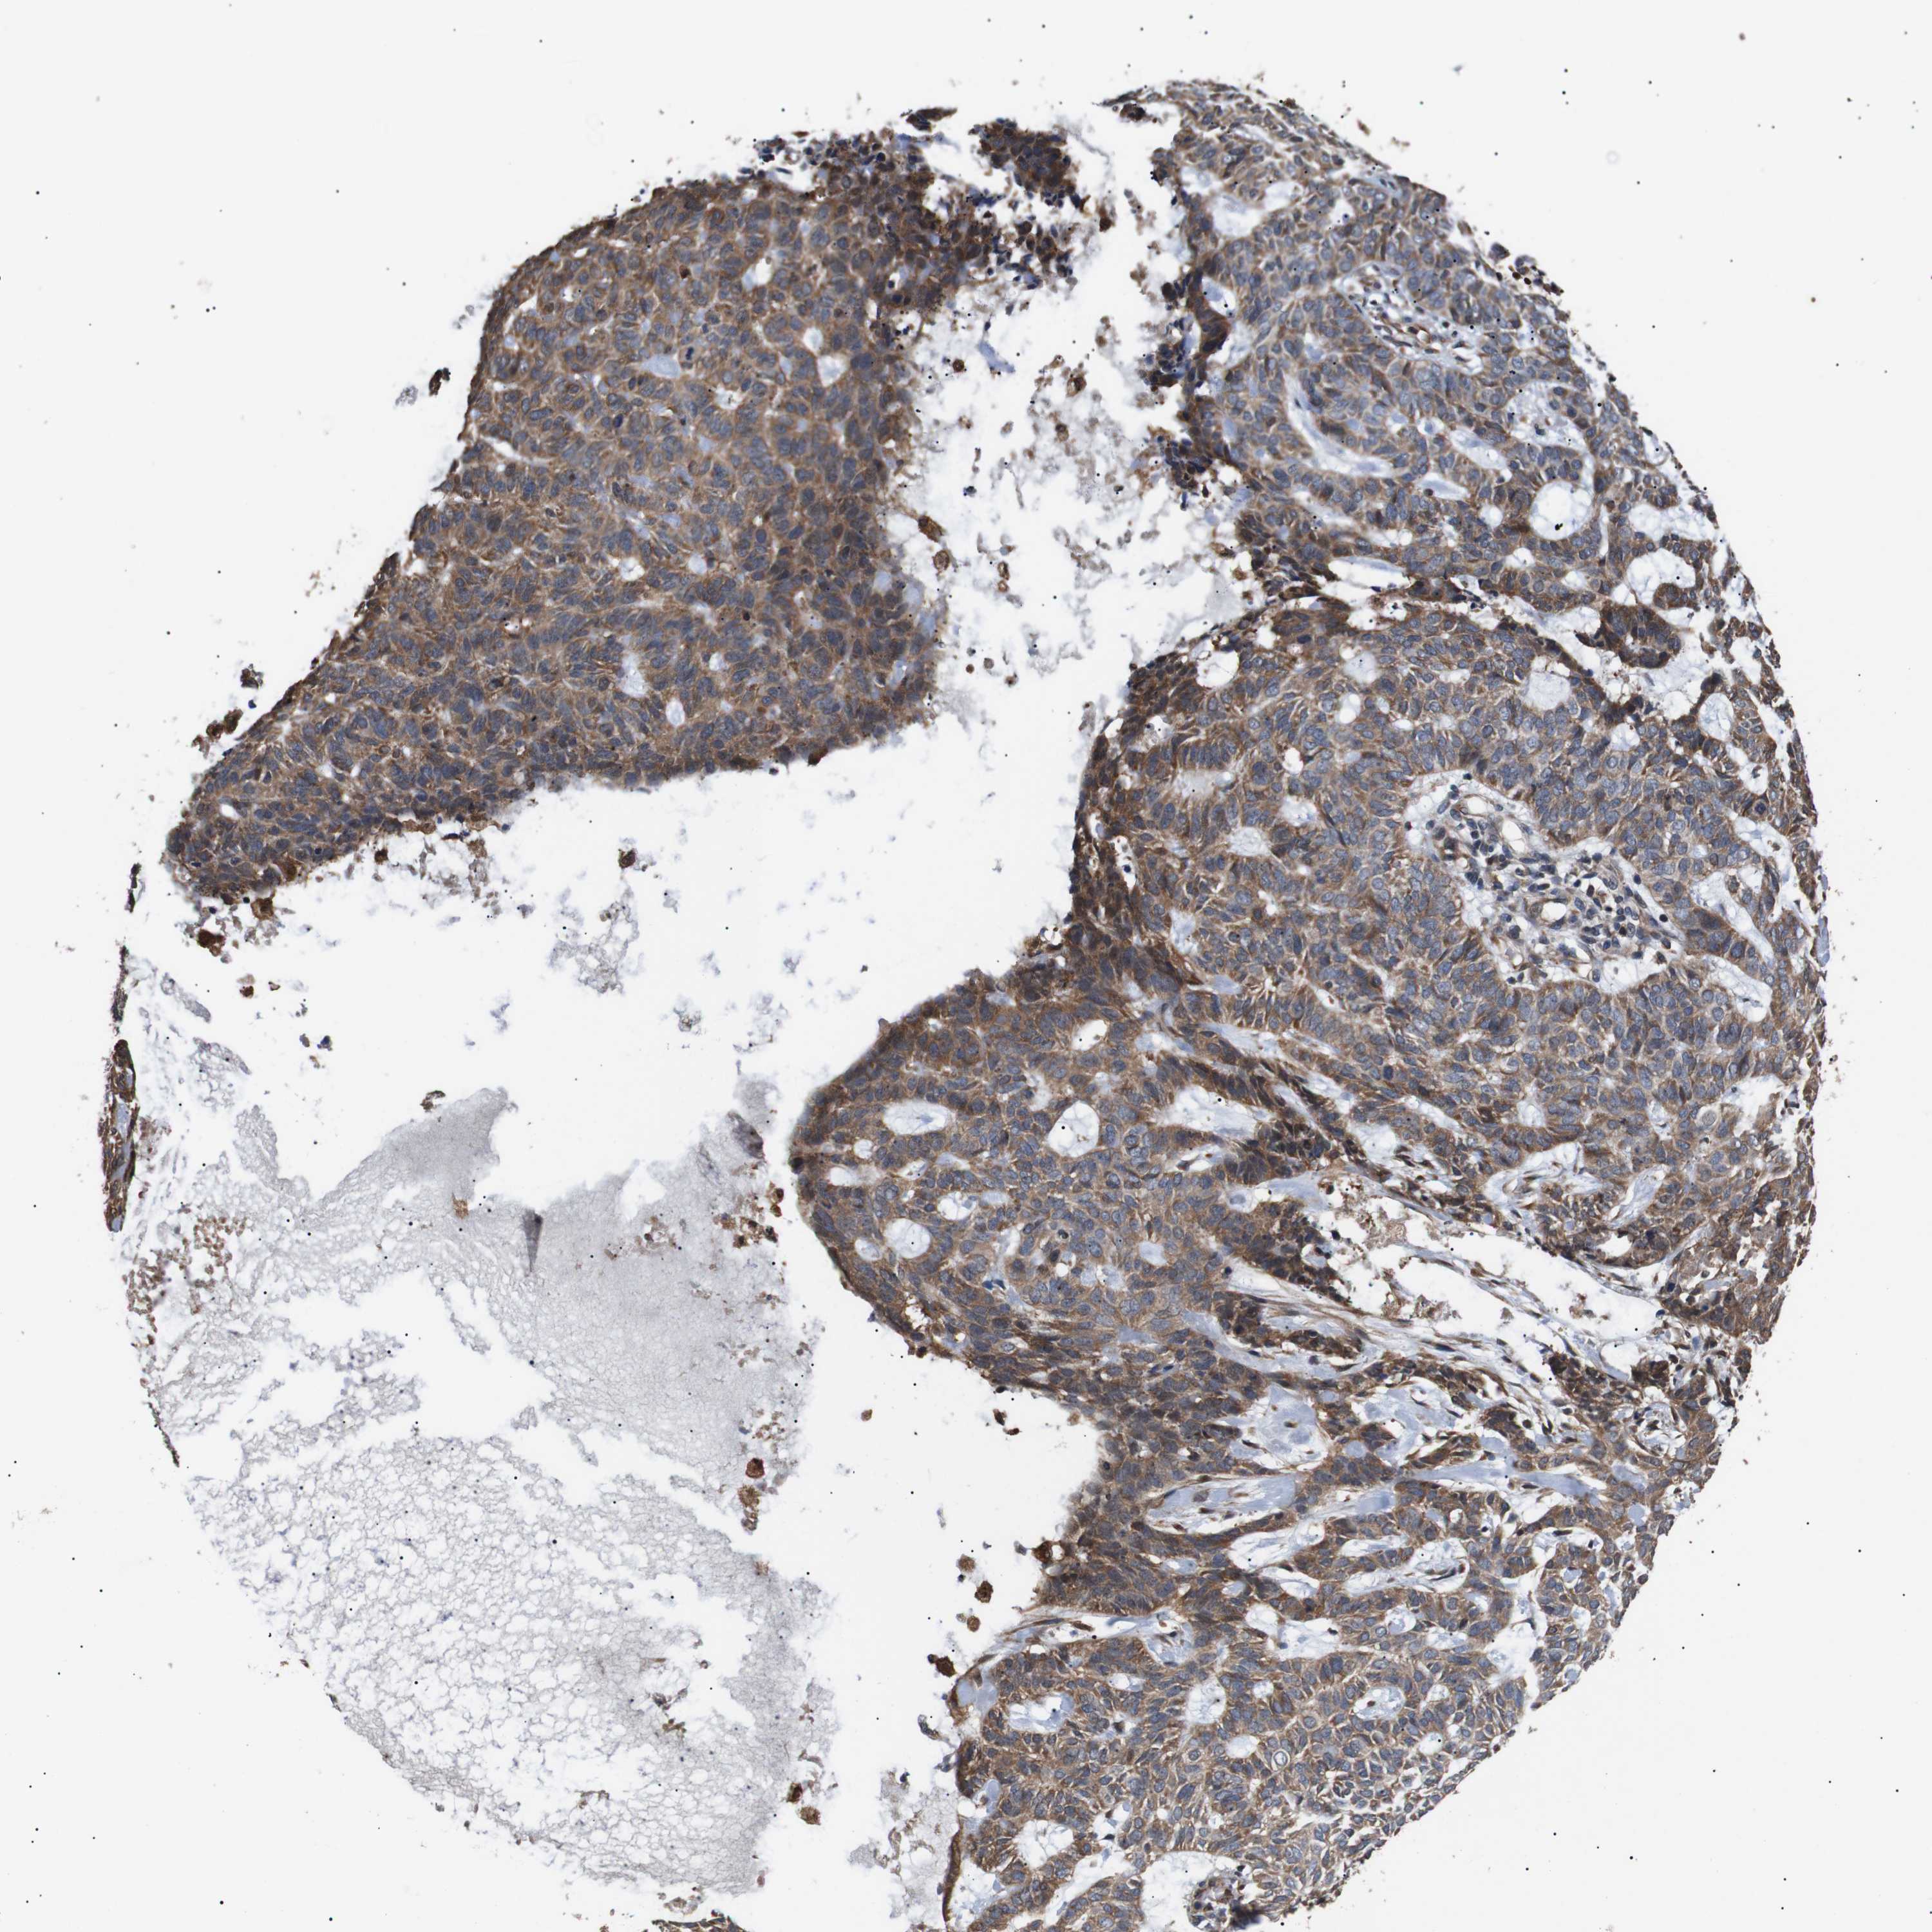

SKIN CANCER - Protein expressioni

A mouse-over function shows sample information and annotation data. Click on an image to view it in a full screen mode. Samples can be filtered based on level of antibody staining by selecting one or several of the following categories: high, medium, low and not detected. The assay and annotation is described here.

Antibody staining in the annotated cell types in the current human tissue is reported as not detected, low, medium, or high, based on conventional immunohistochemistry profiling in selected tissues. This score is based on the combination of the staining intensity and fraction of stained cells.

Each image is clickable and will lead to virtual microscopy that enables deeper exploration of all samples and also displays staining intensity scores, fraction scores and subcellular localization as well as patient and tissue information for each sample.

Antibody CAB010162

Staining

High

Squamous cell carcinoma, NOS